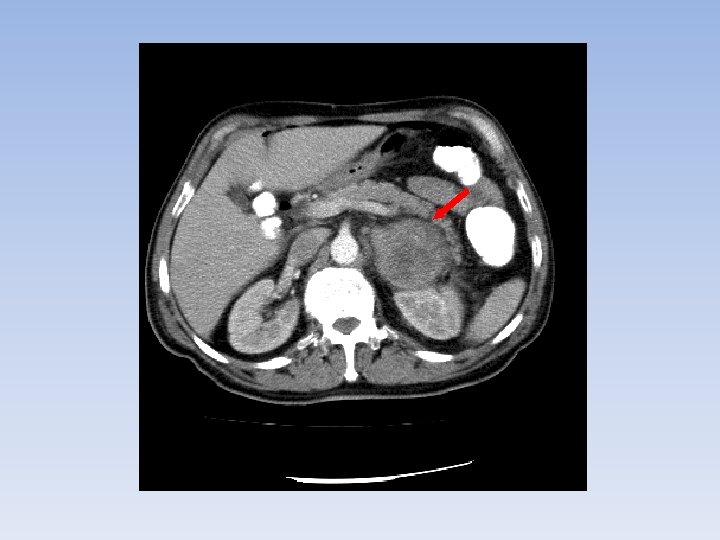

DIAGNÓSTICO TAC Tamaño: subestima. Malignidad. Crecimiento. Ø Heterogéneo. Irregular. Invasión estructuras adyacentes. Adenopatías. Distancia cortes máximo 1 cm.

DIAGNÓSTICO RMN: Sens ~ TAC Inyección de gadolinio: señal en tumores malignos. Lesiones pequeñas.